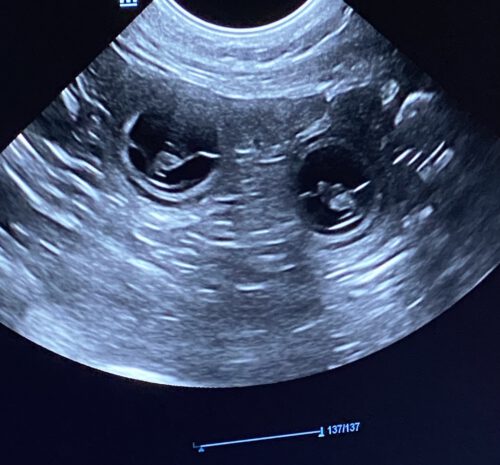

ja was soll ich sagen: Galaxy ist TRAGEND!

Ich bin so happy und freue mich auf die kommende Zeit. Das Galaxy etwas abgenommen hat, ist nicht bedenklich. Sie frißt derzeit schlecht und vor dem Ultraschall habe ich ihr noch kein Frühstück gegeben. Pünktlich zum Frühlingsanfang hat Galaxy die Adonisröschen gefunden und wir im weiteren Ultraschall nicht nur 2 Baby’s 🐶🐶

Galaxy 03/2026 Ultraschall